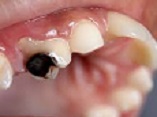

This special issue delves into the intricate world of head and neck disorders, encompassing the oral cavity, salivary glands, thyroid, pharynx, larynx, and craniofacial structures. Bridging the gap between foundational science and clinical innovation, this collection explores the full spectrum of diseases—from benign conditions like dental caries, periodontal disease, and temporomandibular joint disorders to malignancies such as oral squamous cell carcinoma, HPV-driven oropharyngeal cancers, and salivary gland tumors. By integrating dental, oral, and craniofacial health into the broader head and neck framework, this issue highlights the interconnectedness of these systems and their collective impact on patient well-being.